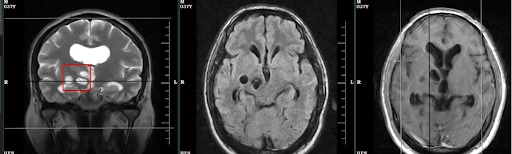

artery of percheron infarcts

Small acute infarcts involving bilateral thalami at paramedian aspect (artery of percheron infarcts). Associated multifocal...